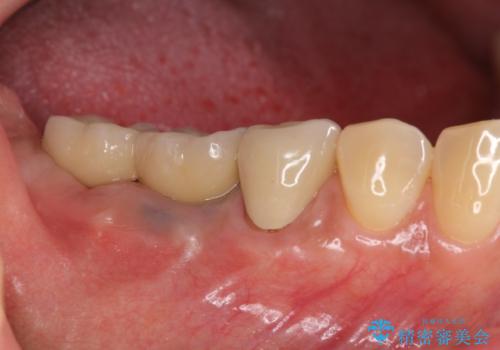

[ 臼歯部インプラント治療 ] 抜けた歯を治療したい

![[ 臼歯部インプラント治療 ] 抜けた歯を治療したいの症例 治療後](https://seimitsushinbi.jp/wp/wp-content/uploads/2022/06/3d94cd3d2c3bb38c4cb75b95fbdde67e-500x350.jpg?v=1655972093)